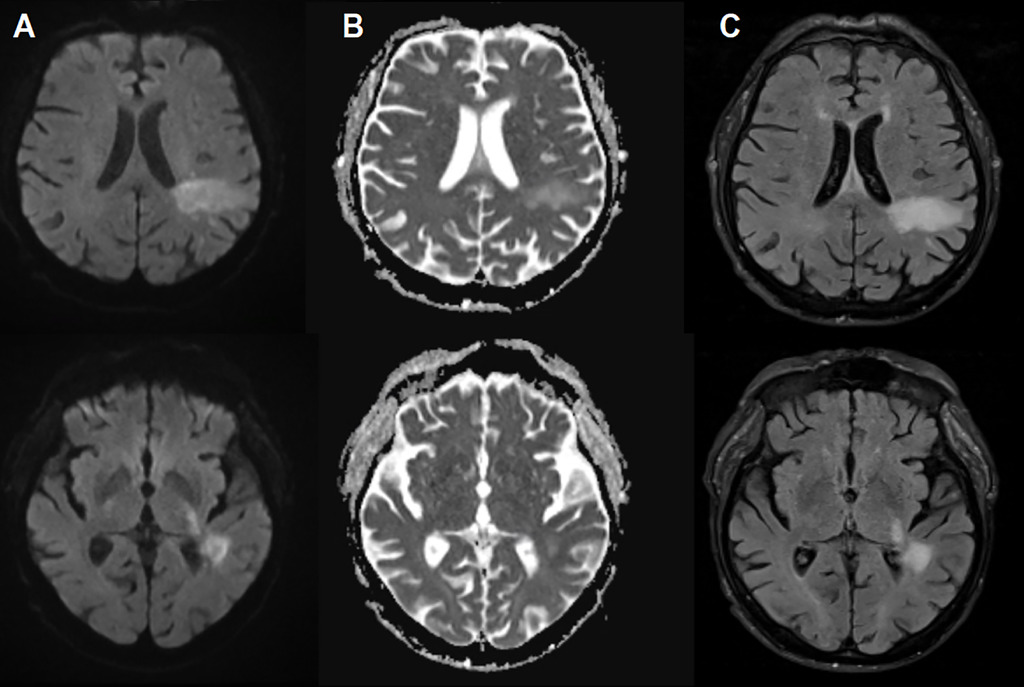

医生起初怀疑这是尿毒症引发的脑病,但在入院 48 小时后,患者的语言障碍急剧恶化。经过脑部核磁共振(MRI)扫描,医生在其大脑白质中发现了典型的脱髓鞘病变。